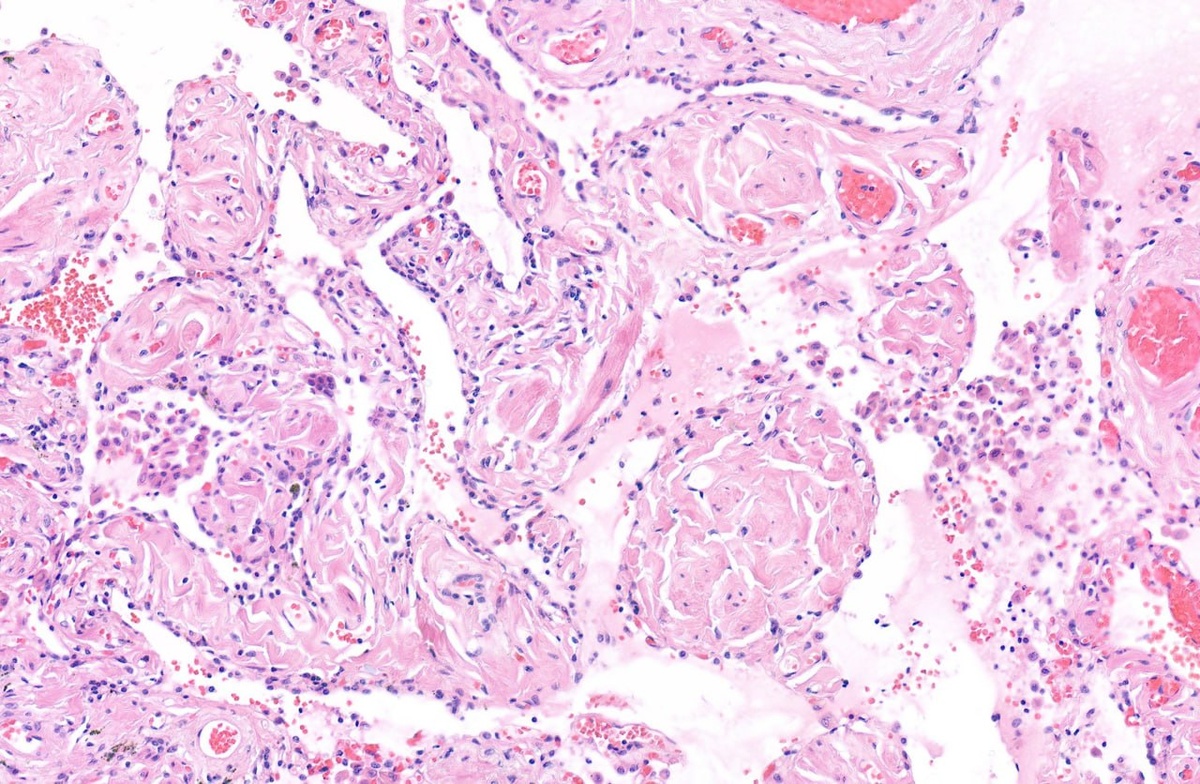

Эмфизема лёгкого. Извитые коллагеновые волокна и слабо пигментированные макрофаги

#легкое #гистология